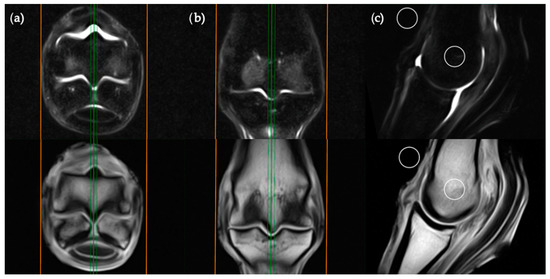

The sagittal plane measurements required three different images for ROI placement; parasagittal slices through the centre of the lateral and medial condyles of the third metacarpal/metatarsal bone (Figure 3) as well as a third image on sagittal midline (Figure 4). In the absence of an image perfectly centred of any of these anatomical locations then the adjacent image containing the greatest amount of STIR hyperintensity was chosen. This was commonly required for the sagittal image ROI. Condylar ROIs were placed at the edge of the subchondral bone plate within the centre of the palmar/plantar half of the lateral and medial condyles. The axial physeal ROI was placed within the axial portion of the bone at the level of the physeal vasculature. The background ROI was placed at the dorsal surface of the limb, proximal to the sagittal ridge of the third metacarpal/metatarsal bone.

Figure 3. STIR FSE (top row) and T1W GRE (bottom row) MRI images in (a) transverse; (b) frontal and (c) sagittal planes; demonstrating the location of condylar ROI placement in a parasagittal plane. The green lines on the transverse and frontal images show the standardized orientation and location of the medial or lateral condylar parasagittal slices for ROI placement. The orange lines show the extent and orientation of all the sagittal slices acquired in the MRI study.